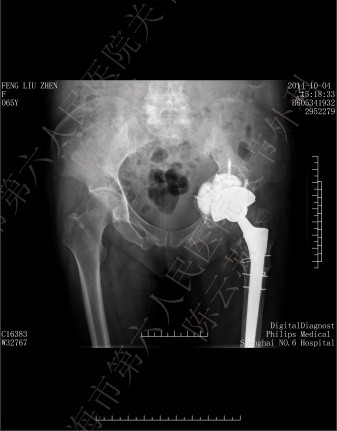

采用个性化人工垫块重建髋臼周围骨缺损的两例患者,手术中及术后影像学检查均证实个体化人工垫块与髋臼面骨缺损匹配完全,固定牢靠,髋臼假体安放及螺钉置入位置及角度理想,无血管神经损伤等并发症出现。目前两例患者分别随访1年及六月,X光片复查臼杯及垫块均固定在位,周围骨组织长入良好。

图3

患者。女性,65岁,左全髋关节置换术后18年,疼痛12年,加剧2年。图1:术前,图2:CT模拟设计,图3:3D打印模块,图4:术中缺损填充,图5:术后片,图6:术后1年随访片